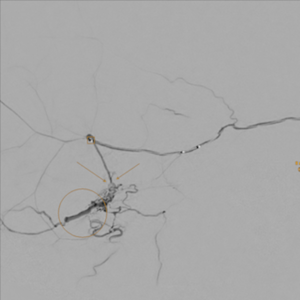

Diagnostische Darstellung der dAVF in der Neuroradiologie:

Das über einen großen Katheter (rechts unten im Bild) gespritzte Kontrastmittel zeigt die zuführende Arterie, den Fistelpunkt (Kreis) und die erweiterte Drainagevene.

Die neuroradiologische Therapie:

Ein sehr kleiner Katheter (Quadrat markierte Katheterspitze) wird über die Hirnhautarterie bis kurz vor den Fistelpunkt (Pfeile) gebracht. Es gilt nun mittels Klebe-Embolisat den Fistelpunkt zu verschließen und somit den hohen Druck von der Drainagevene (Kreis) zu nehmen.